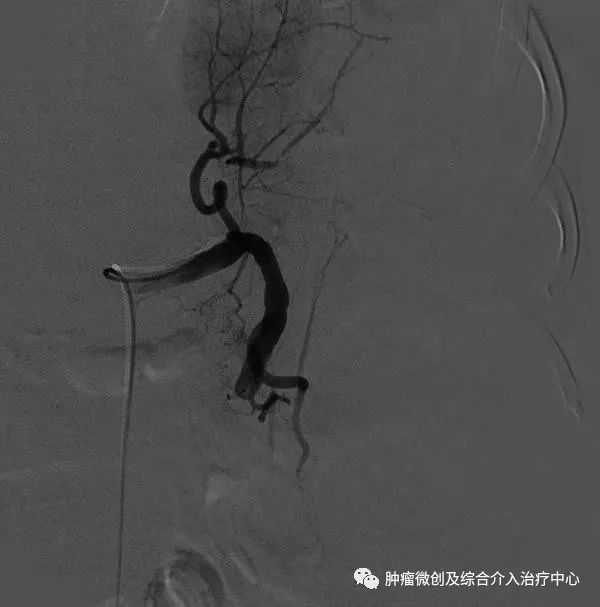

4.再次脾动脉造影,明确脾栓塞程度。若感不足,可补加栓塞,直至满意为止。退出导管,穿刺处压迫止血后加压包扎,平卧24h。